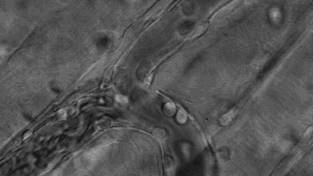

人体内的T细胞正在找寻病菌并进行击杀

巡逻”中的T细胞

每个T细胞大约是人类头发直径的十分之一,它们在人体内不断巡逻,找出并杀死癌细胞或感染了危险病毒的细胞。

当T细胞发现癌细胞时,通过分泌的毒素附着在癌细胞上,来检测、分辨正常细胞与癌细胞。

查明之后,T细胞连接癌细胞,打破癌细胞外壁,向其表面引入毒性蛋白。

一旦细胞毒素进入,癌细胞会逐渐衰弱、死亡。而T细胞继续在人体内巡逻,寻找下一个目标。